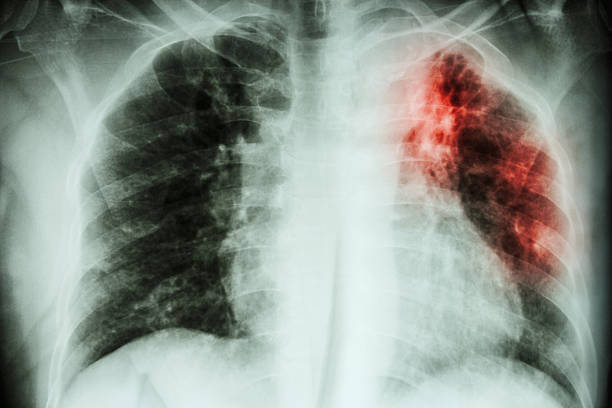

Туберкулезный процесс представляет собой болезненное самочувствие, которое сложно поддается лечению. Пациенты, сумевшие побороть недуг, отмечают, что противотуберкулезная терапия могла длиться у них годами, оставив после себя ряд осложнений и негативных последствий. Почему так сложно избавиться от болезни? Дело в том, что микобактерии туберкулеза обладают многоуровневой защитой, а поэтому резистентные к большинству противобактериальных препаратов, резким температурным перепадам, ультрафиолетовому излучению и тому подобное. К тому же, после проникновения в человеческий организм, они быстро снижают функцию иммунной системы, что делает невозможным процесс избавления от них. Туберкулез нуждается в массовой профилактике, так как ежегодно уносить миллионы жизней людей, не имеющих специфической защиты от инфекции.

Туберкулезная инфекция относится к числу самых распространенных заболеваний по всему земному шару, которое диагностируется у людей разных возрастных групп, независимо от их пола, расовой принадлежности и социального положения в обществе. Согласно официальной статистике, сегодня в мире насчитывается более 1,6 млрд. больных туберкулезом, практически половина из которых страдает тяжелыми формами болезни и активно заражает своих окружающих. Единственной профилактической мерой, позволяющей предупредить заболевание, в настоящее время является прививка против туберкулеза. Хотя даже своевременная и полноценная вакцинация не дает уверенности, что человек не заболеет. Тогда, нужна ли прививка от туберкулеза? Зачем ее ставят и какую вакцину лучше при этом выбрать?